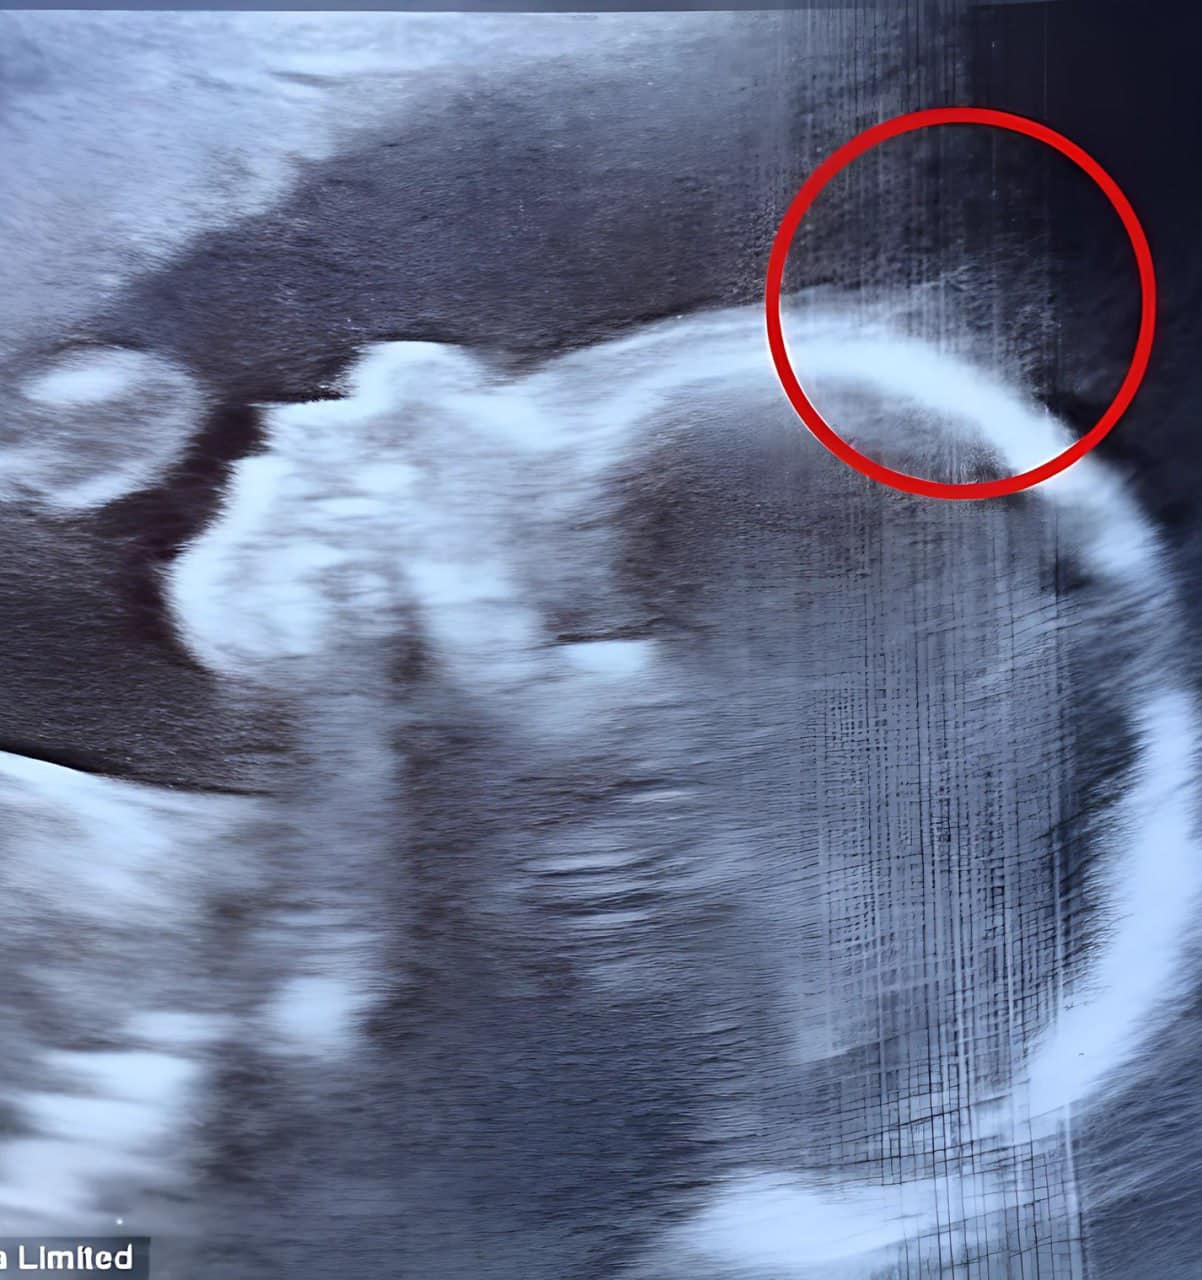

When 28-year-old Natasha Gent of the United Kingdom had her 20-week ultrasound, both the doctors and Natasha herself noticed anything peculiar about the image.

After some discussion, they determined that it was hair and that the baby would most certainly be born with a full head of hair. However, when Natasha saw her daughter after birth, reality exceeded even her boldest expectations.